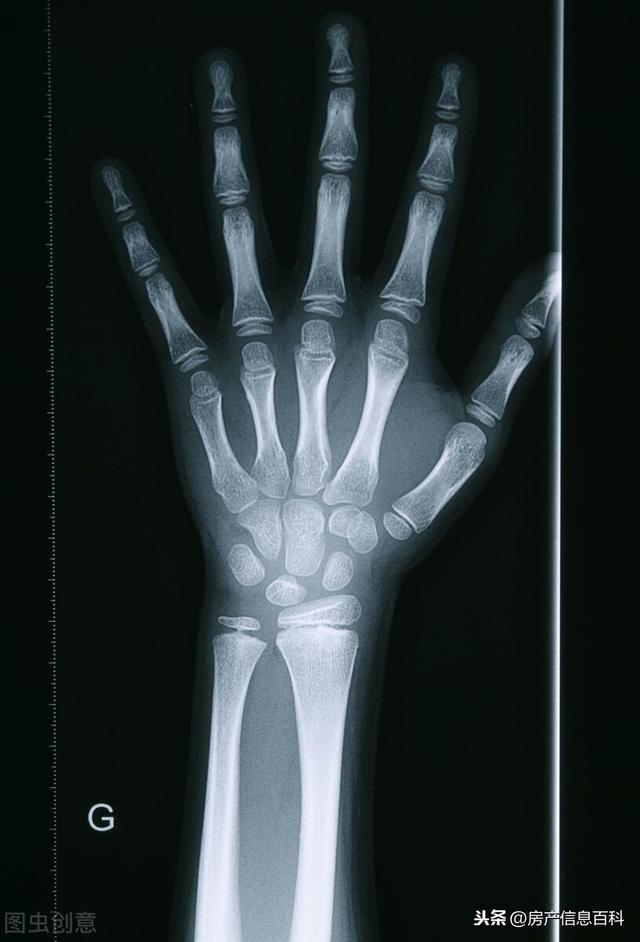

父母也不懂什么骨龄检测,打听了一下,还是带着孩子去了市里面医院检测,他孩子13岁,骨龄已经有15岁了,所以想要读初中和高中突然长高概率不是很高了,他初高中会长个,但长个已经很有限了,老师给他讲了一些原理,整理如下:

决定孩子的未来身高并不是你的生理年龄,而是你的骨龄,

骨骺线有没有闭合,是否还处于生长期的阶段,如果骨骺线处于闭合状态,要长个子可能性不大。